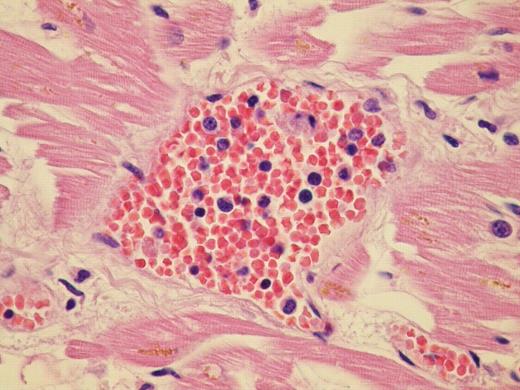

Myeloid metaplasia – myocardial localization

We report the case of a 60 year old patient with advanced Post Thrombocitemia Myelofibrosis extensively localized in almost all organs. He was referred to our Center in April 2008; clinical, radiological and haematological features suggested an evolution into Myelofibrosis. Molecular analysis for V617F JAK2 mutation was negative. Hemogram showed leukocytosis, mild anemia and normal platelet count. After few months of treatment with Danazol and Thioguanine, he was admitted for hemodynamic failure; echocardiography and chest X-ray were normal; abdomen CT scan confirmed important splenomegaly and didn't show any deep thrombosis. During hospitalization he developed massive intracerebral haemorrhage, cause of death. Post mortem histopatological examination documented osteomyelosclerosis and wide localization of extramedullary hematopoiesis. Morphological examination of the specimens showed an extensive dissemination of megakaryocytes, erythroid and myeloid precursors immunoreactive with factorVIII, hemoglobin, and myeloperoxidase respectively. We documented intravascular involvement of spleen, liver, lymph nodes, lungs, adrenal glands, myocardium, and central nervous system. Noteworthy fibrosis associated with haematopoietic cells were broadly distributed into retroperitoneal tissue.